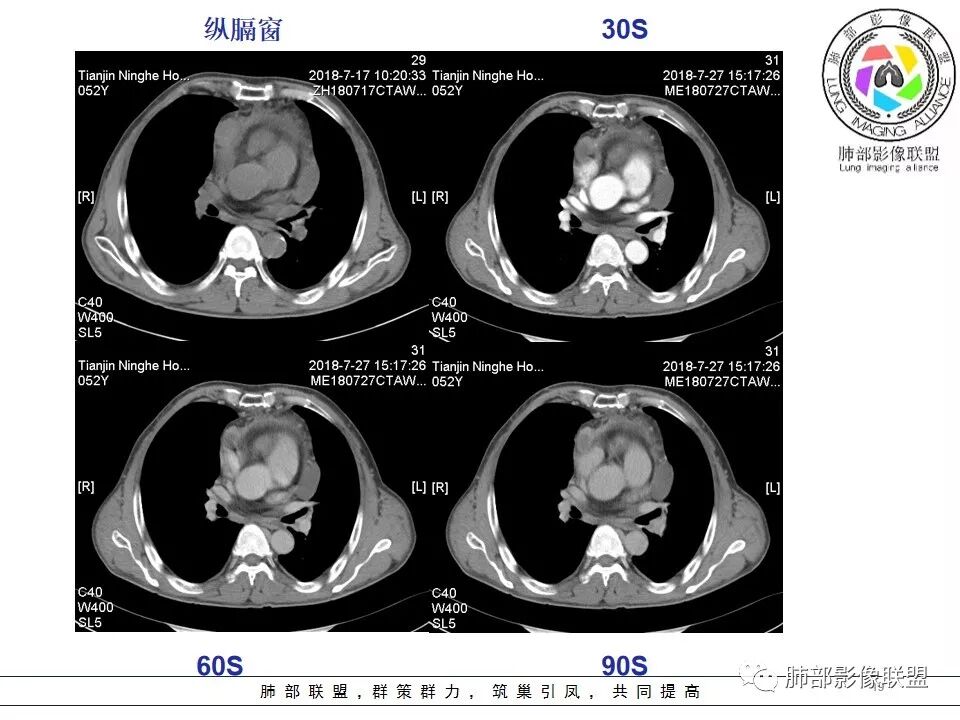

南边:强化就不用说了

侵袭性胸腺瘤?胸腺癌?老年,钙化、肿大淋巴结,边缘侵犯、累及心包、侵犯上腔静脉——支持

b.密度不均匀,囊变坏死多见,纤维分隔影少见,有钙化---多见于高危胸腺瘤及胸腺癌以上,尤其大片囊变坏死多见于B1型以上胸腺瘤跟胸腺癌;钙化多见于肿瘤实质内,非边缘区,多发的泥沙样、微钙化及多形性钙化多见于B2、B3型;

b. ①纵隔脂肪间隙模糊、胸膜、心包侵犯、膈肌受累--见于高危胸腺瘤及胸腺癌,但是心包侵犯多见于B3胸腺瘤跟胸腺癌

②纵隔大血管侵犯、肺转移、膈神经麻痹、淋巴结转移及远处血行转移---多见于胸腺癌,B3胸腺瘤罕见

1.  病灶内实质性钙化,提示AB型以上胸腺瘤、胸腺癌或类癌,其中微钙化往往提示高危型胸腺瘤跟胸腺癌、类癌,同时也排除了淋巴瘤(淋巴瘤不会有钙化);

2.  病灶呈分叶蔓延倾向,其内大片状囊变坏死,周围脂肪间隙模糊,提示高危型胸腺瘤或胸腺癌,但是类癌周围脂肪间隙往往很清晰;

3.  胸膜、心包侵犯,多提示高危型胸腺瘤中的B3型胸腺瘤、胸腺癌、类癌

4.  纵隔淋巴结肿大及纵隔大血管(上腔静脉)受侵犯,提示胸腺癌或类癌。

5. 此患者NSE增高,提示神经内分泌肿瘤可能,纵隔神经内分泌癌最常见的是不典型类癌,胸腺类癌临床上可伴相关临床表现。肿瘤体积巨大,边缘清晰,强化显著(与鳞癌不同),肿瘤内边缘规则的管状血管影(鳞癌内血管是破坏、纤细、僵硬);